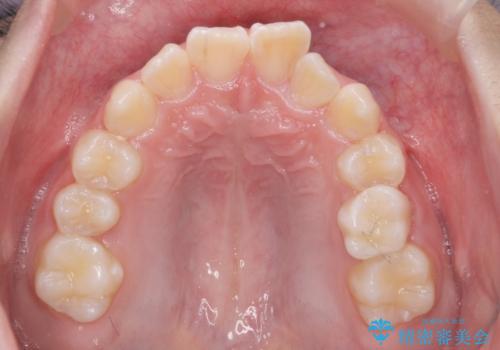

子供の出っ歯 生え代わりと成長期を利用して非抜歯で矯正

- 出っ歯を主訴に来院。

生え代わりを待ってから矯正を始めました。

特に右側のかみ合わせがずれていたため、上の奥歯を後ろに下げています。

下顎も前方に成長し、前歯のかみ合わせも同時に深かったのを浅くすることができました。